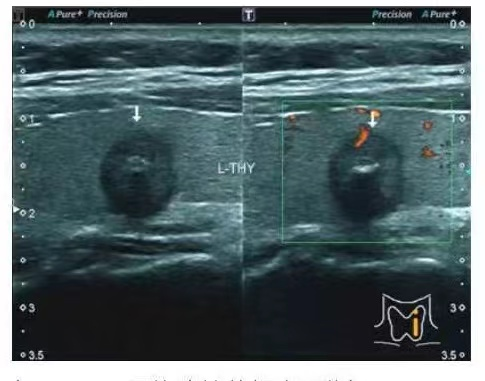

东芝Aplio500全身高端彩色多普勒超声诊断仪,应用多种成像技术,可适用于腹部、甲状腺、乳腺、腔道、心脏、血管、胎儿等多脏器项目检查,其中该诊断仪特有的超声微血管成像技术(SMI),可敏感显示占位内的新生血管,为占位良恶倾向性判断提供更为精准的科学依据。

(王丹主任为患者检查甲状腺) (甲状腺结节超声图像)